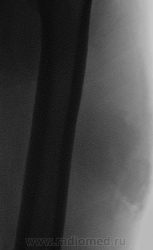

- https://radiomed.ru/sites/default/files/styles/case_slider_image/public/user/117/_073318000000.png?itok=fPXQ37s5

По плотности - липома, чтобы высказаться о ее характере, надо бы снимок побольше, захватив целиком окружающие мягкие ткани и кость, и посмотреть в мягкотканном и костном режиме. Но можно сделать и МРТ (КТ)...

Поддержу МРТ, да и иголочкой можно кольнуть.

Я тоже пока что в этом деле лось, но думаю дело поправимое, на днях улетаю С-Петербуг в МАПО(цикл КТ и МРТ), ну да ладно, что косается пациента то он ещё в 2007 году обращался по месту жительства к травматологу по поводу ушиба бедра с формированием гематомы, была назначена местная рассасывающая терапия, до 2009г. видимо ждали пока рассасется в декабре обратился к хирургу по поводу посинения и увеличения в объёме задней поверхности бедра, назначен гепарин в феврале был вскрыт абсцесс в этом месте, далее только в марте сподхватились по УЗИ-мягких тканей признаки образования, ну и открытая ножевая биопсия: Описание изменений, выявленных при микроскопическом исследовании: в материале фрагменты опухоли, представленной пучками вытянутых клеток с полиморфными гиперхромными, местами уродливыми ядрами. Определяется значительное количество митозов, встречаются поля некроза опухоли. При иммуногистохимическом исследовании опухолевые клетки экспрессируют виментин, отсутствует реакция на десмин, гладко-мышечный актин, S100. Патоморфологическое заключение: саркома мягких тканей, боее вероятно фибросаркома.